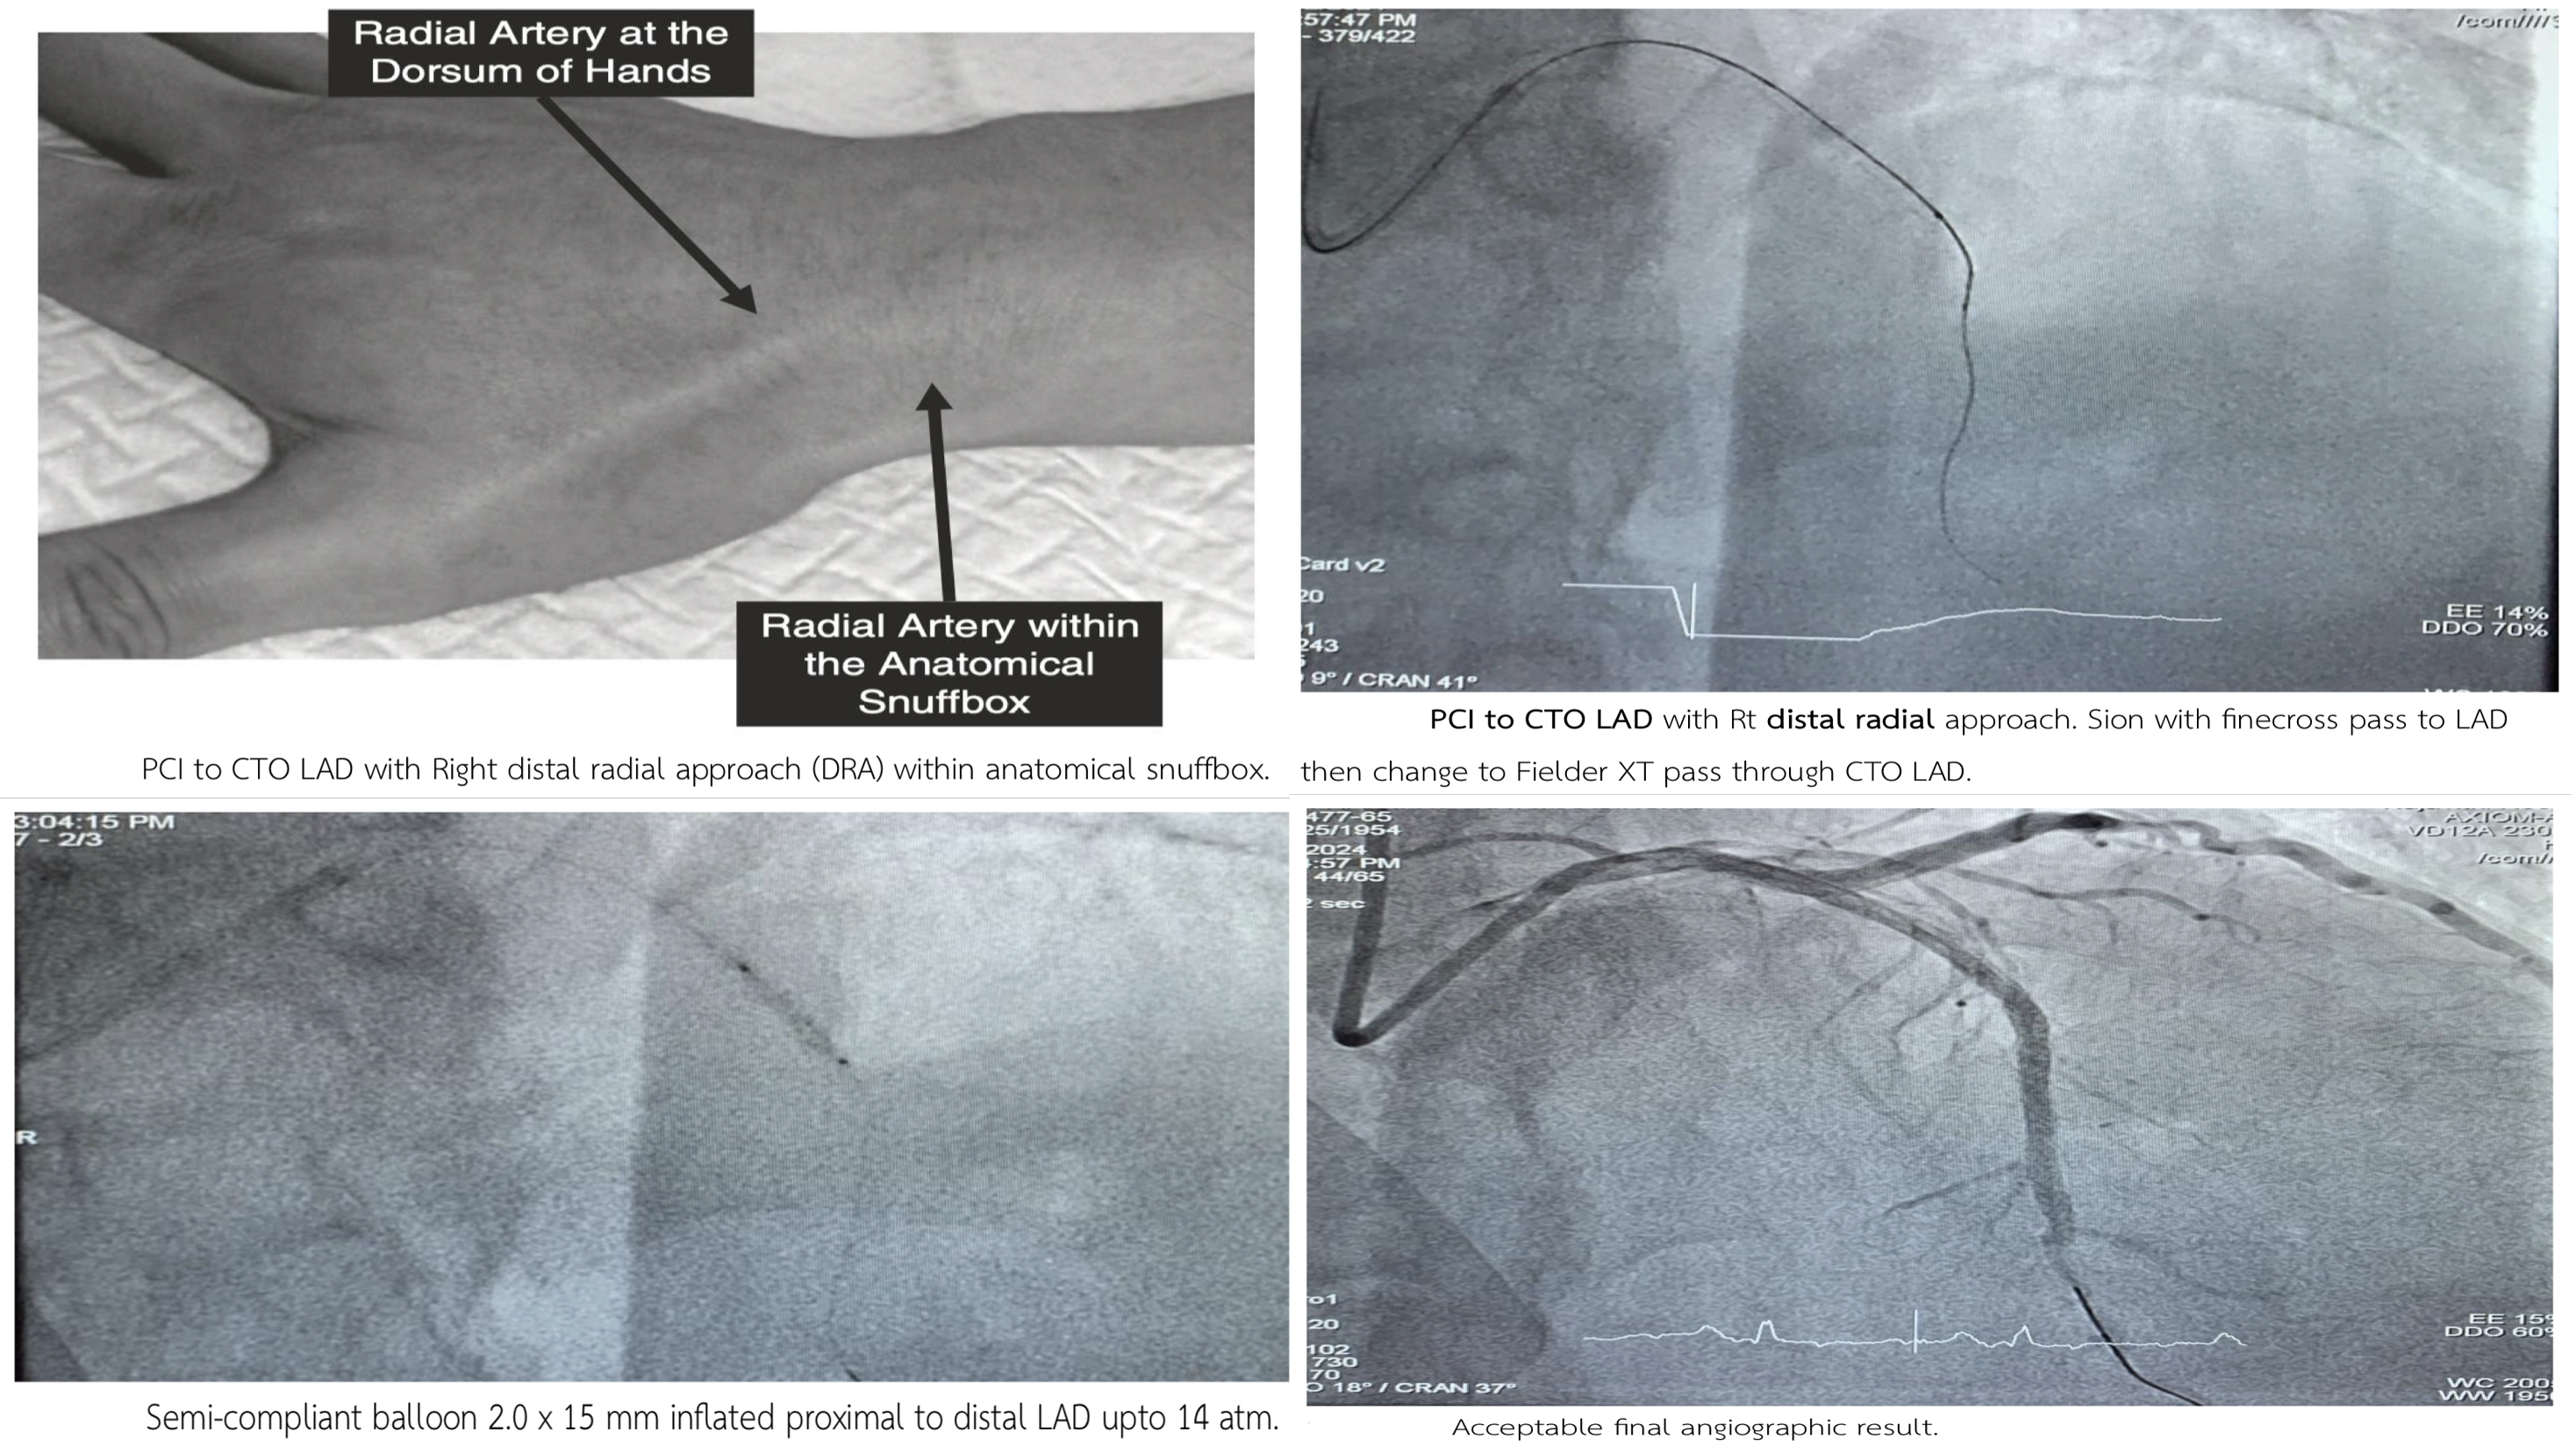

PCI to culprit RCA via Rt radial. GD: 5 Fr Ikari Stenting p-d RCA with Resolute integrity 2.5 x 22 mm upto 12 atm. The patient still had chest pain then stage PCI to CTO LAD with Rt DRA. Staged PCI to CTO LAD via Rt DRA. GD: 5 Fr Ikari Sion with finecross pass to LAD then change to Fielder XT pass through CTO LAD. Tip injection revealed true lumen wiring . SC balloon 2.0 x 15 mm inflated p-dLAD upto 14 atm. Xience ProA 2.5 x 38 mm deployed m-d LAD upto 12 atm. Resolute integrity 2.75 x 30 mm deployed p-m LAD upto 12 atm. Acceptable angiographic result.

1. DRA is a feasible and safe alterative for complex PCI. 2. Complex CTO LAD can be successfully treated with a right DRA and a 5 Fr Ikari . 3. PCI for CTO using a 5 Fr radial Ikari can be successful in selected cases.